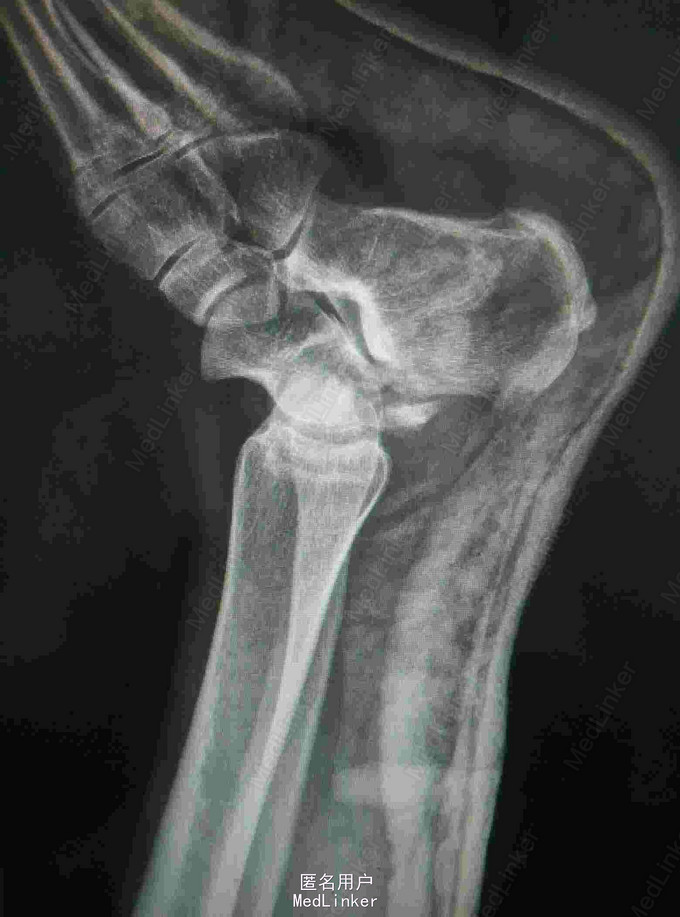

患者外伤致左踝关节疼痛肿胀,活动受限2天 患者中年女性,因外伤致左踝关节疼痛肿胀,伤后即无法站立,踝关节活动受限,于当地医院石膏外固定后入我院。

查体:左踝关节肿胀明显,局部皮肤压痛,无皮损及皮下淤斑,踝关节活动受限,各足趾感觉正常,足背动脉搏动存在。 辅查:我院CT提示距骨、足舟骨、跟骨骨折

诊断:左足距骨、足舟骨、跟骨骨折 治疗:距骨骨折切开复位内固定术

随访:石膏固定4-6周,3月内禁止负重,定期复查。 讨论:患者X线片对左足骨折显示不够清楚,基本常规行CT,可以看到明显的距骨骨折,累及关节面,需手术复位关节面。足舟骨以及跟骨骨折未明显移位保守处理。